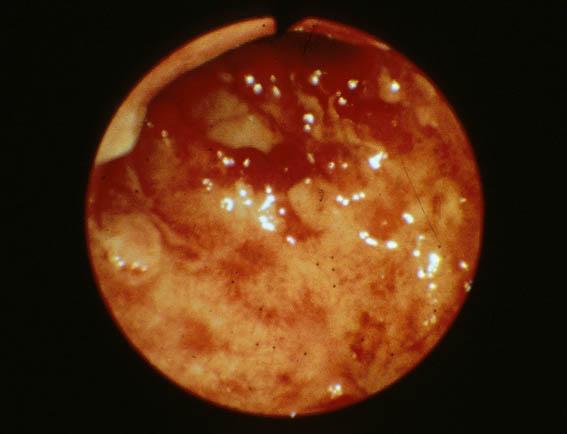

Poliposis Inflamatoria que se evidenció en Colitis Ulcerativa (caso 1)

[Image-ID:1730]

Lesión que asemeja tumoración/Poliposis Inflamatoria

parte(separada por órganos)

colon/otros

método de exámen

Endoscopia

diámetro mayor del tumor

20 - 24